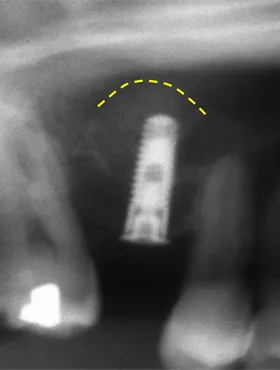

奥歯を1本長期間失ったケース

■治療前

向かって左の下の奥歯が、長期間失ったまま放置されていました。その為、向かって左奥の2本の歯が、前に倒れるように傾いてしまっていました。

まず、この傾きを治しました。治療期間は4ヶ月です。

■治療中

■治療後

■治療中レントゲン写真

その後、歯を失った場所には、人工の歯根であるインプラントを埋めて、白い歯をかぶせました。

■治療後レントゲン写真

このようにして、従来なら前と後ろの歯を削って治していくブリッジにせずに、治すことができました。

| 主訴 | 右下の奥歯をずいぶん前に抜きそのままにしていたら、奥歯が倒れてきた |

| 治療方法 | 部分矯正治療+インプラント治療 |

| 治療期間 | 約10か月 |

| 通院回数等 | 12回位 |

| 費用 | 約80万円 |

| リスク・副作用 | インプラント術後の腫れ・痛み |